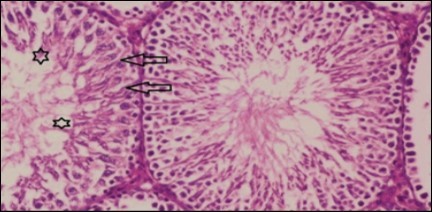

Histological examination of control rats' testis showed normal histological structure of the seminiferous tubules with an increase in the spermatogonia and other spermatocytes compared with the diabetic rats which showed an obvious decrease in the count of germinal cells generally and sloughing of germ cell in the lumen of seminiferous tubules in addition to absence of the mature sperms (Figure 3 and Figure 4). Rats tested of Fenugreek group and those treated with Glimepiride (Figure 5 and Figure 6) presented an increase in the number of spermatogenic cells and mature sperms with few focal necrotic cells. Whereas the combination therapy group showed normal histological structure of the seminiferous tubules with normal spermatogonia, presence of ledying cells and more mature of sperms (Figure 7). STZ reduced testosterone production, suggesting a decrease in the function of both Leydig (testosterone producing cell) and Sertoli (spermatogenesis) cells, which might be caused by a reduction in insulin secretion. These changes are probably due to increased Reactive Oxygen Species (ROS) production by accelerated Advanced Glycation End Products (AGE) formation 31 hexosamine and Protein Kinase C pathway. The administration of Fenugreek seeds to diabetic rats significantly decrease of sperm shape abnormality and improve the sperm count 32. Glimepiride reduced sperm abnormality and increased testis weights and sperm count by its antioxidant action 30. The potential protective efficacy of Fenugreek seed extract when added to Glimepiride was observed on reproductive systems.

Figure 4.Photomicrogragh of testis section of diabetic rat showing the sloughing of germ cells towards lumen of seminiferous tubules, absence of spermatozoa with low height of germinal epithelium and congested wide interstitial tissue (star). (H&E) (40x).